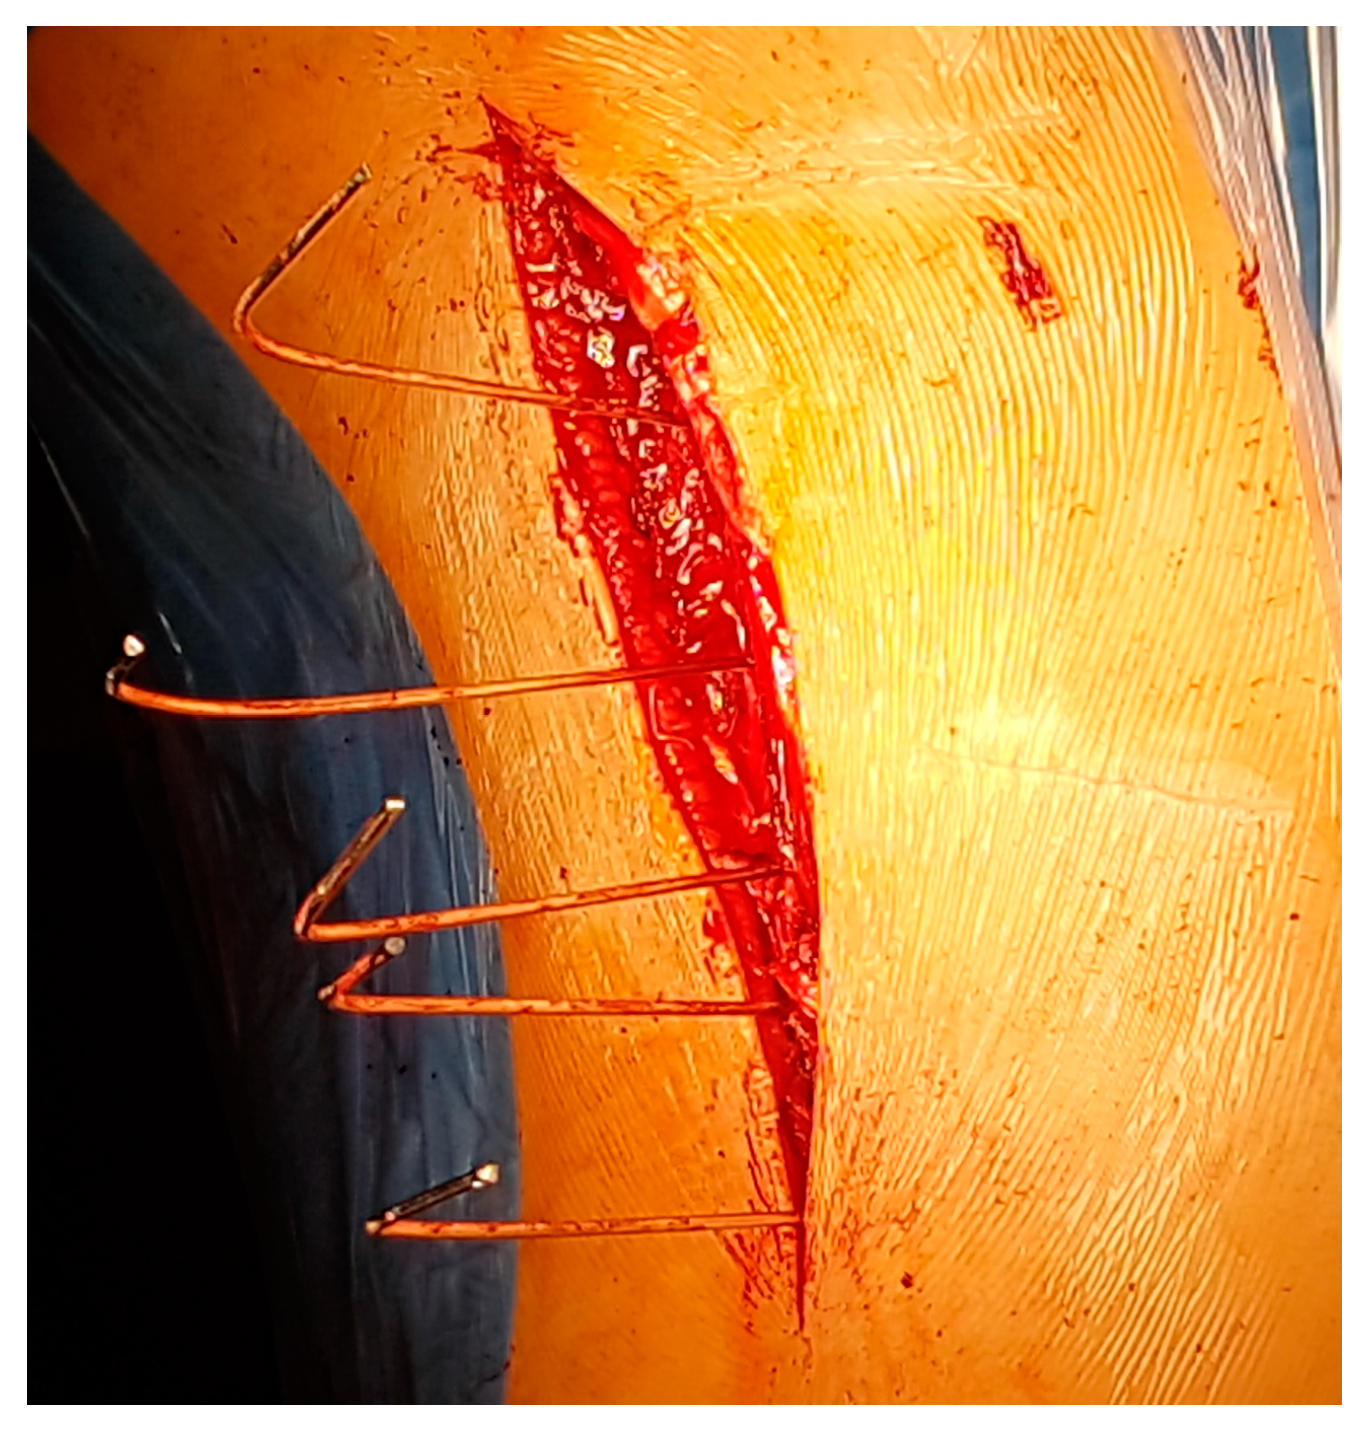

2.2. Surgical Technique